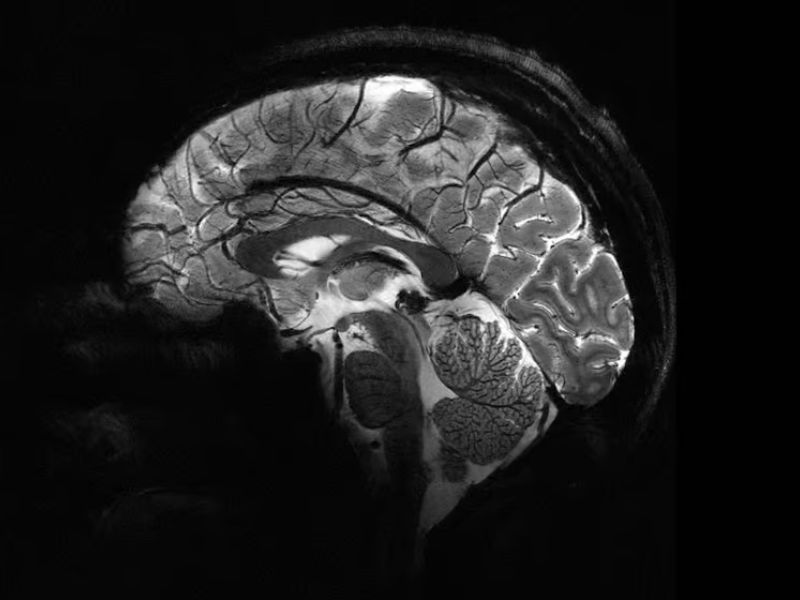

The world’s most powerful MRI machine has begun to demonstrate its capabilities by conducting scans of living human brains. These images offer an ultra-high-resolution view of the brain, aiding in our comprehension of consciousness and the treatment of neurodegenerative conditions.

The Iseult MRI machine can acquire images of brain tissue horizontally at a resolution of 0.2 mm (0.008 in) in slices just 1 mm (0.04 in) thick, all within a mere four minutes. This volume equates to imaging a few thousand neurons simultaneously.

A few years ago, Iseult underwent testing using pumpkins, but it has now conducted scans on its first human subjects, comprising 20 healthy volunteers. These remarkable images showcase the potential of the new MRI technology to uncover previously inaccessible insights into brain function, including the encoding of mental representations and the neuronal signatures linked to consciousness.